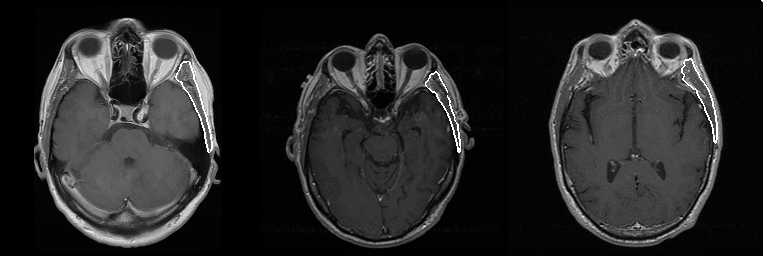

Figure 1. Example of automatically produced temporalis muscle segmentations.

For this task, we first manually produced segmentations of temporalis muscle using a touch screen to act as the ground truth of which some are used for training, and some are used to evaluate the accuracy of the automated segmentations. We took an already implemented version of a U-Net, which is a type of neural network commonly used in medical image segmentation tasks and tried to make it work with our local dataset. After some time of getting grey images instead of the desired output segmentation – an image where the pixels belonging to the object to be segmented are assigned one value, and pixels belonging to the background, are assigned another value – we explored the usage of a different loss function, on which the neural network is trained, which improved the model performance. At the end of my placement, we had a model that performed moderately well with the similarity between manually and automatically produced segmentation being 90%.

Although our initial exploration of using deep learning in temporalis segmentation was successful, we knew there were room for improvement. One of the main drawbacks was that the model was trained on a relatively low number of images and all of them came from the same local dataset with a limited number of patients. To address this issue, we searched for external datasets that could be used. In our current work we used local and publicly available datasets to re-train the model. We then performed survival analysis using two datasets - local and TCGA-GBM, as these had survival data. With this work we managed to train a neural network with high accuracy – mean Dice score of 0.893 ± 0.045, Jaccard index of 0.809 ± 0.072 and Hausdorff distance of 1.889 ± 0.354 mm. Overall survival was significantly longer in patients with higher temporalis muscle CSA in both the local dataset (median OS 22.4 vs 14.5 months) and TCGA-GBM (15.4 vs 12.9 months). Progression-free survival was also longer in the local dataset for the patient group with higher CSA (median PFS 14.3 vs 6.4 months). Thus, we were able to validate our initial work with using additional external datasets and further added to the evidence that temporalis muscle is predictive of outcomes in brain tumour patients.